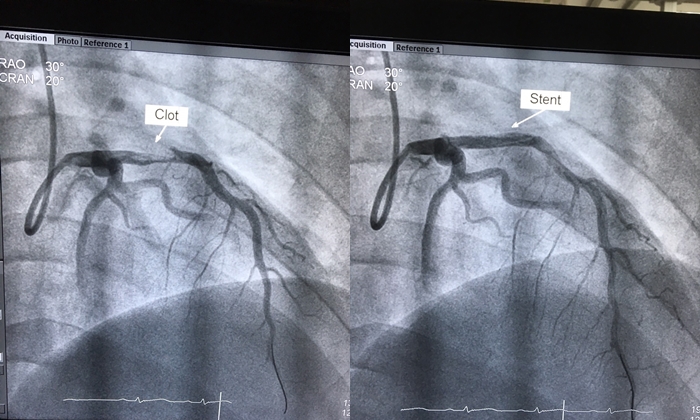

6 อาการตอนตื่นนอน ที่อาจเป็นสัญญาณ "หลอดเลือดหัวใจอุดตัน" โดยไม่รู้ตัว

แพทย์จากจีนเตือนว่า ตอนเช้าเป็นช่วงที่เลือดข้นกว่าปกติ ความดันโลหิตและอัตราการเต้นของหัวใจอาจเพิ่มสูงขึ้นอย่างรวดเร็วจากระบบประสาทอัตโนมัติที่ถูกกระตุ้น ประกอบกับการที่หัวใจต้องทำงานหนักขึ้น อาจทำให้ผู้ที่มีภาวะหลอดเลือดหัวใจตีบหรืออุดตัน แสดงอาการผิดปกติอย่างชัดเจน ดังนี้

บางคนอาจรู้สึกเหมือนมีของหนักกดทับหน้าอก หายใจไม่ออก หรือหัวใจเต้นแรงผิดปกติโดยไม่มีเหตุผล นี่อาจเป็นสัญญาณเริ่มต้นของโรคหลอดเลือดหัวใจอุดตัน

อาการเจ็บแปลบกลางหน้าอกหรือบริเวณใกล้หัวใจ โดยเฉพาะในตอนเช้า อาจรุนแรงถึงขั้นลามไปยังไหล่หรือแขนซ้าย เป็นสัญญาณเตือนชัดเจนของโรคหลอดเลือดหัวใจตีบ

แม้อาการเหล่านี้อาจไม่ใช่สัญญาณของโรคหัวใจทุกครั้ง แต่หากเกิดซ้ำบ่อยๆ ควรไปพบแพทย์เพื่อตรวจสุขภาพหัวใจ เพราะ “กล้ามเนื้อหัวใจตายเฉียบพลัน” (Heart Attack) สามารถเกิดได้กับทุกวัย และมีอัตราการเสียชีวิตสูงหากไม่ได้รับการช่วยเหลือทันท่วงที